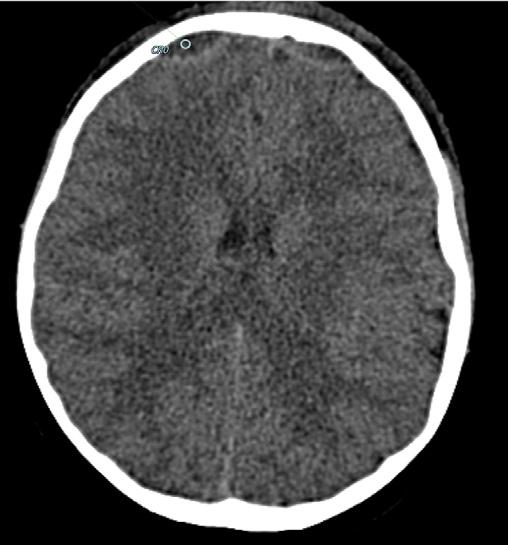

67 Cefalea… occhi aperti

Giuseppe Paviglianiti, Elisa Costantini, Gianluca Coscia, Floriana Di Marco, Vittorio Messina, Domenico Cipolla, Angelo Spataro